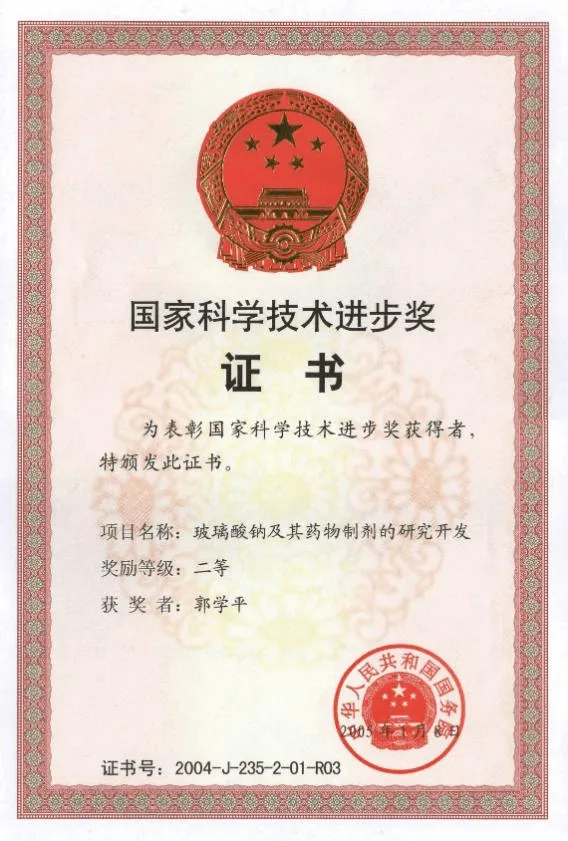

华熙生物成立于2000年,作为一家全球领先的生物科技与生物制造企业,公司率先实现抗衰核心物质透明质酸的生物制造,市场份额常年全球第一,并以此优势为基础打开了对糖生物学和细胞生物学的前沿研究。依托公司建成的全球最大合成生物制造平台,华熙生物致力于将生命科学成果转化为应用于衰老干预、组织再生等领域的创新解决方案,目前已构建起了一个从原料到终端产品,涵盖医药、医美、营养科学和皮肤科学的整合解决方案,推出了润百颜、夸迪、米蓓尔、肌活、华熙当康等品牌。秉持“让每个生命都是鲜活的”企业使命,持续推动健康与美丽事业的发展。